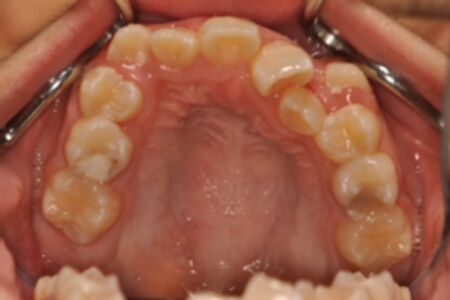

| 治療内容の詳細 | 初診時10歳の女性で、全体的ながたつきを主訴として来院されました。 検査の結果、交叉咬合を伴う、アングルⅠ級不正咬合と診断しました。 治療としては、反対咬合を改善するための装置で上顎前歯部を前方にだすと同時に上あごを広げ、セルフライゲーションブラケット装置(デーモンシステム)で歯の配列を行いました。 治療期間は2年11か月でした。 |